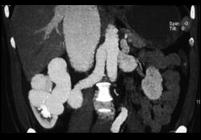

男,18岁,请根据所示图像,选择最可能诊断 ( )A、右侧肾癌B、右肾动静脉畸形C、右肾出血D、右肾囊肿E、右肾积水

问题 男,18岁,请根据所示图像,选择最可能诊断 ( )

选项 A、右侧肾癌 B、右肾动静脉畸形 C、右肾出血 D、右肾囊肿 E、右肾积水

答案 B